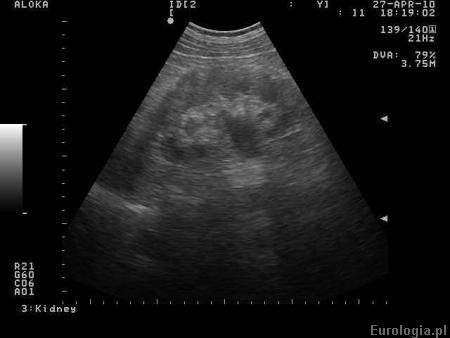

Fot. Obraz nerki z zastojem w UKM.

Poszerzenie UKM - zastój moczu w układzie zbiorczym nerki obserwowany jest w badaniach obrazowych układu moczowego - np. USG, urografii lub tomografii komputerowej. Zastój moczu w UKM świadczy o utrudnionym odpływie moczu z nerki, którego przyczyna zawsze wymaga diagnostyki.

Zastój moczu w układzie kielichowo miedniczkowym nazywany jest zwyczajowo wodonerczem. Określenie wodonercze nie oddaje w rzeczywistości rzeczywistego stanu nerki. Zgodnie z definicją wodonerczem nazywa się nerkę, w której występuje poszerzenie układu kielichowo - miedniczkowego ze współistniejącym zwężeniem warstwy miąższowej.